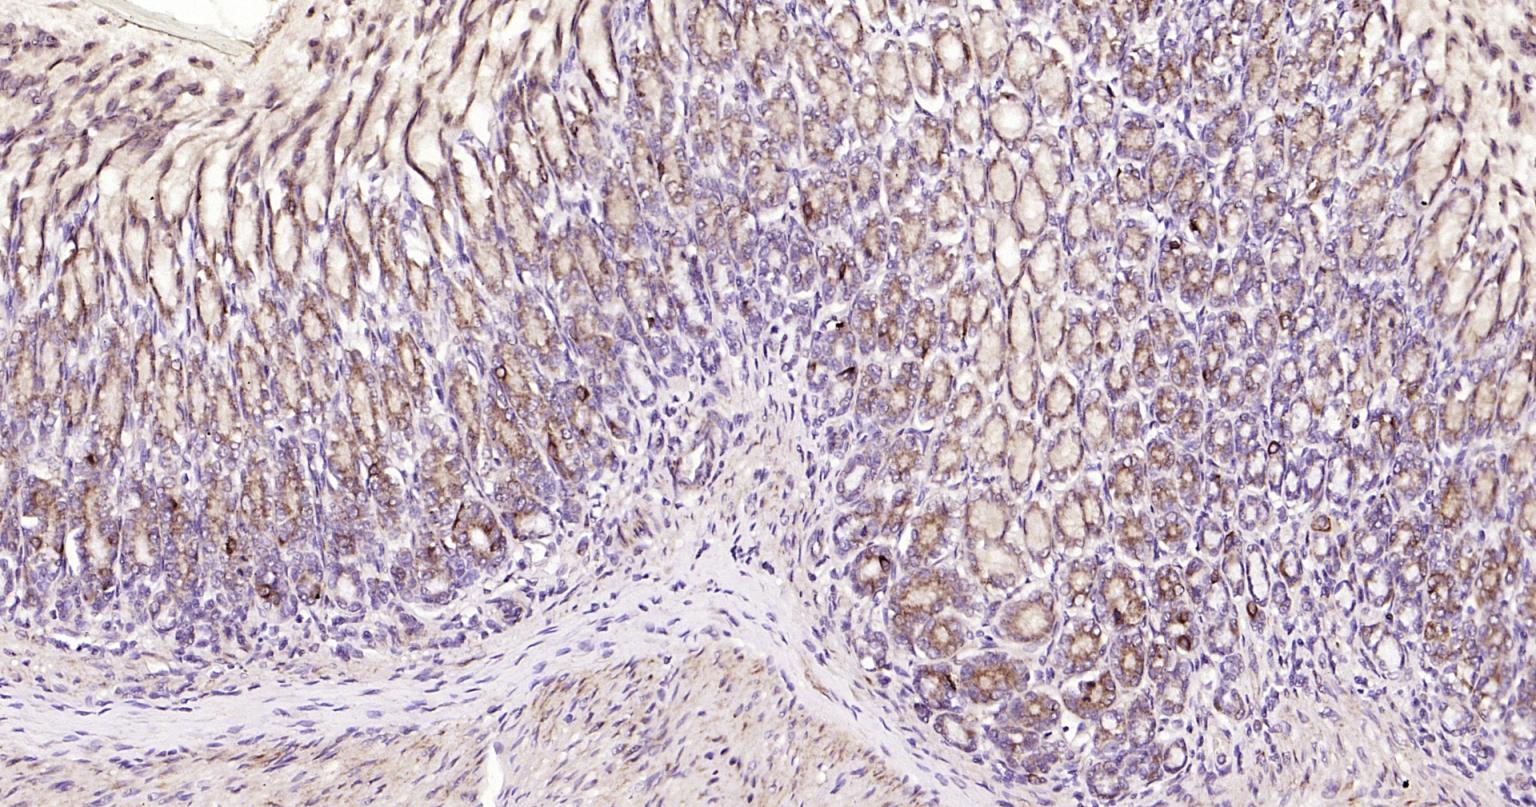

| IHC-P | Human, Mouse, Rat | Rabbit | 1:400-800 |